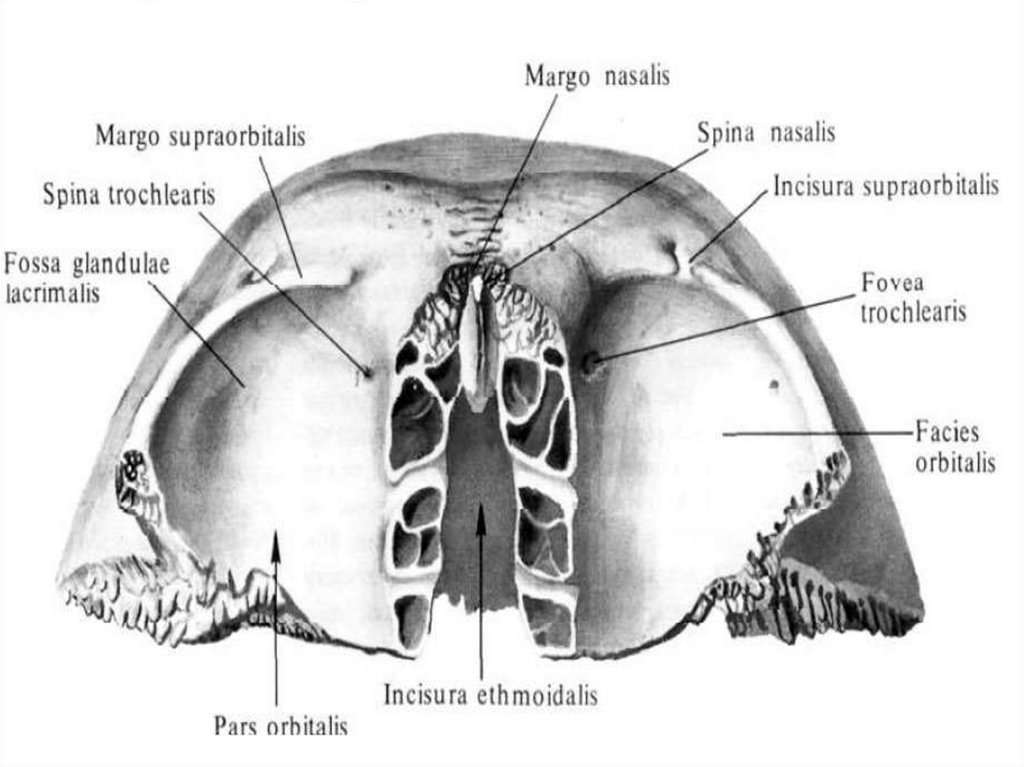

Анатомические изображения срединной сагиттальной линии черепа